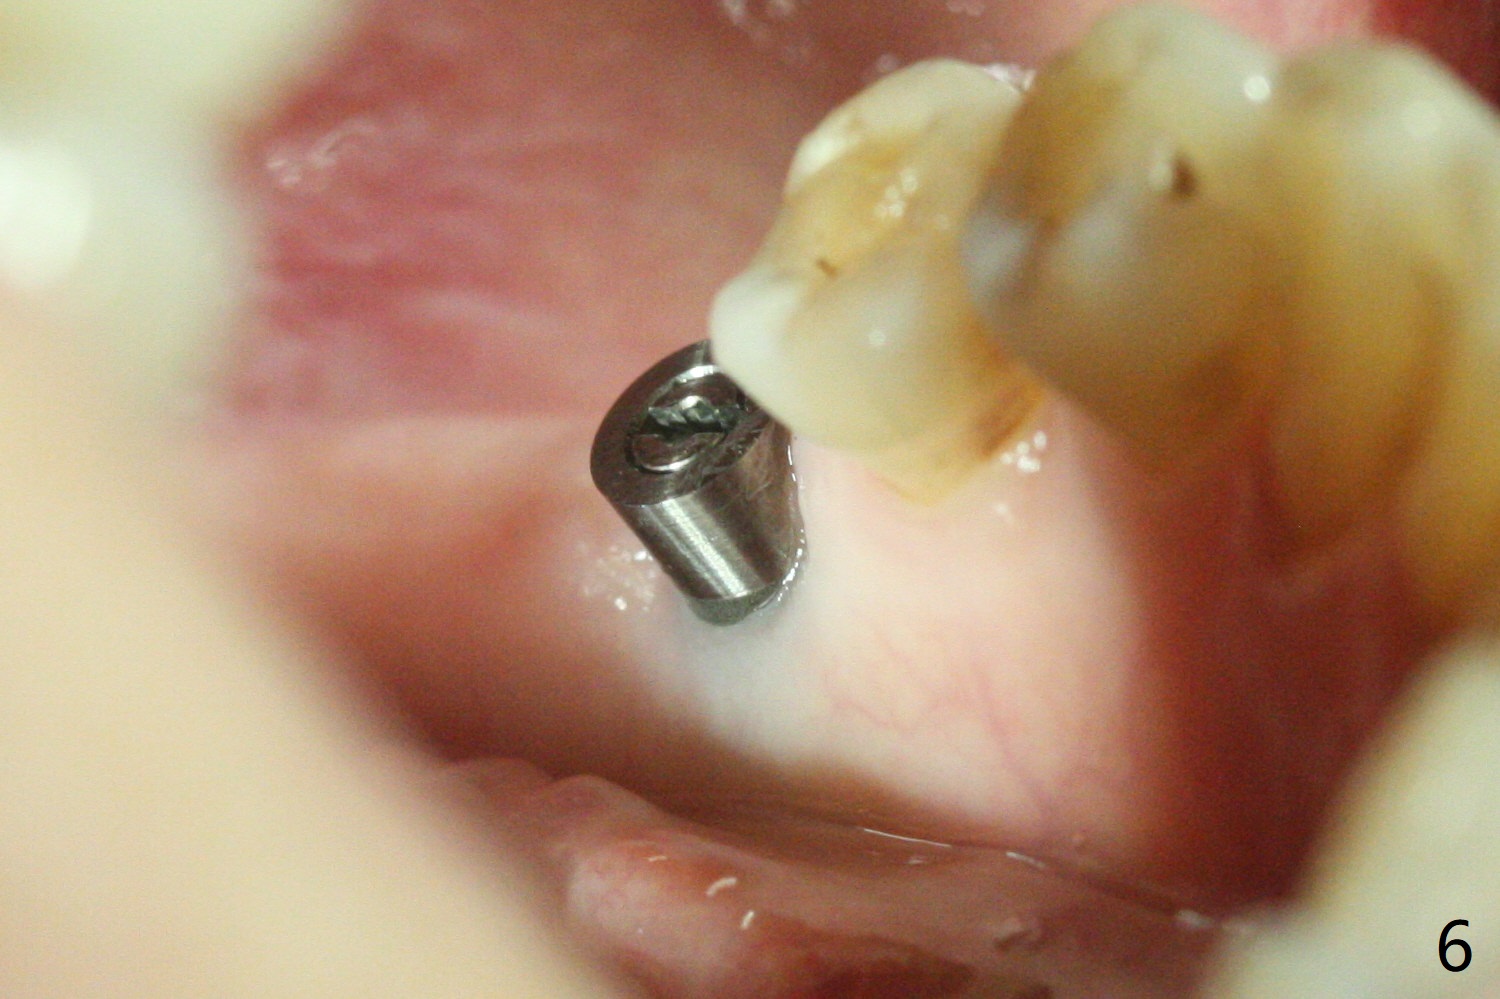

Following light use of 4 mm tissue punch, a buccal incision is made and raised. After 4x8.5 mm drill with 10.5 mm offset at #19, 4.5 mm cortical drill is used for 2/3 length to take care of the thick dense lingual plate (overprep). The remaining apical 3 mm osteotomy is underdrill (3.5 mm). After try-in of a 4.5x14 mm tissue-level dummy implant, a same-sized definitive one obtains 35 Ncm torque (Fig.1). Following 3-4 more turns, the torque reaches 45 Ncm (Fig.2) with the distal thread covered (<) and autogenous bone graft placed in the distal defect (*). A 4x3 mm unipost is placed to keep periodontal dressing in place. Clinically the implant is placed within bone boundary buccolingually. The new implant seems necessary considering short (Fig.2 S) and probably resorbed (Fig.1 R) roots of the premolars. In fact the short abutment keeps the mesiolingual portion of periodontal dressing for 2 weeks; since local hygiene is suboptimal, the healing screw is placed after abutment and dressing removal (Fig.3).